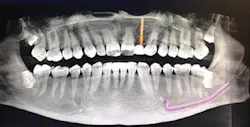

A 32-year-old male presented with a congenitally missing lateral, No. 10. The buccal-lingual dimensions were sufficient for standard implant placement, but the mesial-distal dimensions were 4.56 mm (figures 1a and 1b). The patient had a failing Maryland bridge, both functionally and esthetically (figure 2). He was always told that implants were not an option for him unless he underwent significant orthodontic treatment, and even then, nothing was guaranteed.

Figure 1a: Pre-op panorex

A 50-year-old female presented with a missing tooth No. 12 that was extracted for unknown reasons more than 10 years ago (figure 7). The patient was referred to our office for an implant consultation. Upon review of a CT scan, it was revealed that at the widest area buccal-lingually there was 4.09 mm and at the narrowest 3.8 mm (figure 8). She was presented with two treatment options: bone grafting or a narrow-diameter implant. She opted for the narrow-diameter implant, as it eased several of her concerns: she was unhappy with a removable appliance, worried about a block graft for a single tooth, and finances were a burden.

Figure 7: Pre-op panorex